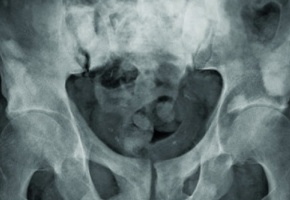

Le Pr Karim Fizazi, chef du département d’oncologie médicale à l’Institut Gustave Roussy, a présenté en conférence plénière au congrès de l’Asco - qui s’est tenu à Chicago du 2 au 6 juin et qui a réuni plus de 25 000 médecins et chercheurs du monde entier- l’étude Latitude, dont les résultats majeurs vont changer la prise en charge des patients diagnostiqués d’emblée d’un cancer métastatique de la prostate. Les données de l’essai clinique ont été publiées également dans le NEJM. Avant 2015, les patients atteints d’un cancer métastatique de la prostate étaient classiquement traités par hormonothérapie conventionnelle afin d’inhiber la fabrication de la testostérone par les testicules. En 2015, trois grands essais cliniques français, anglais et américains ont démontré le bénéfice de l’ajout d’une chimiothérapie au traitement hormonal dès le diagnostic. "Même si le cancer de la prostate est très sensible à une hormonothérapie, nous savons que les inhibiteurs de la testostérone n’éradiquent pas complètement toutes les cellules cancéreuses et qu’il reste une production d’hormone résiduelle", explique le Pr Fizazi, l’investigateur principal de cet essai. L’objectif était de mesurer le bénéfice de l’abiratérone (Zytiga, Janssen) sur la survie globale et la survie sans progression du cancer chez des patients nouvellement diagnostiqués d’un cancer métastatique de la prostate. L’abiratérone est une hormonothérapie de nouvelle génération qui empêche la production d’hormones androgènes par les glandes surrénales et la cellule cancéreuse elle-même. Ce médicament possède une AMM depuis 2012. Il est utilisé actuellement comme arme de rattrapage chez les patients atteints d’un cancer de la prostate métastatique devenu résistant à l’hormonothérapie conventionnelle et en rechute avant ou après une chimiothérapie. "L’étude Latitude démontre que l’abiratérone administrée dès la prise en charge du cancer en plus d’une hormonothérapie conventionnelle diminue d’environ 40 % le risque de décès et de plus de 50 % le risque de rechute du cancer après deux ans et demi de suivi". Ainsi, ajouter un nouvel anti-hormonal au traitement standard contre le cancer agressif de la prostate semble très efficace. Latitude est une grande étude clinique randomisée comparative (double aveugle contre placebo), internationale et multicentrique (235 centres répartis dans 34 pays), de phase III à laquelle 1200 patients ont participé entre février 2013 et décembre 2014. L’essai a comparé chez des patients souffrant d'un cancer de la prostate métastatique à haut risque, nouvellement diagnostiqué et hormono-sensible, un traitement standard de suppression androgénique associé à des placebo (n = 602) à la même suppression androgénique associée à de l’acétate d’abiratérone (1 000 mg/j) et à de la prednisone (10 mg/j) [n = 597]. Les résultats ont démontré que l’ajout de l’abiratérone à l’hormonothérapie conventionnelle améliore non seulement considérablement le pronostic de ces patients (survie globale et survie sans progression de la maladie) mais aussi l’ensemble des complications liées à la maladie. La survenue de complications osseuses (douleurs, fracture, compression médullaire due à l’envahissement tumoral d’une vertèbre) sont décalées dans le temps. Avec ce bénéfice incontestable, l’abiratérone se positionne comme un nouveau standard dans les formes métastatiques à haut risque. "L’avantage de ce médicament est qu’il s’agit d’un traitement oral qui est habituellement bien toléré. Ces importants résultats sont une très bonne nouvelle pour ces patients et nous pensons que le bénéfice sera encore meilleur avec un suivi plus long", espère le Pr Fizazi. La prochaine étape est l’étude européenne Peace-1 promue par Unicancer et dirigée par le Pr Fizazi qui évalue l’adjonction de l’abiratérone à un traitement de base renforcé comportant hormonothérapie conventionnelle et chimiothérapie. Les premiers résultats sont attendus à partir de 2020.